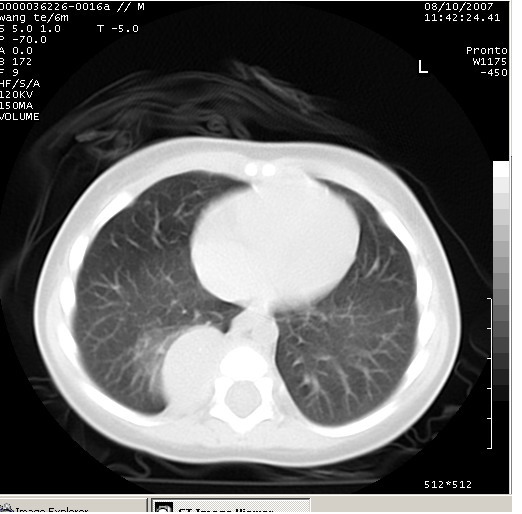

患儿男、6个月,因咳嗽三天曾拍胸片考虑肺部感染,这是在胸片后约一周左右作的ct。

右下肺纵隔旁软组织密度影,边界清楚,内见点状高密度影。支持考虑:神经源性肿瘤!

右下肺纵隔旁软组织密度影,宽基底紧贴胸椎与肋骨,边界清楚,内见点状高密度影。支持考虑:神经源性肿瘤!肺隔离症待排

右下肺纵隔旁边界清楚软组织密度影,内见点状高密度影。考虑:神经源性肿瘤!